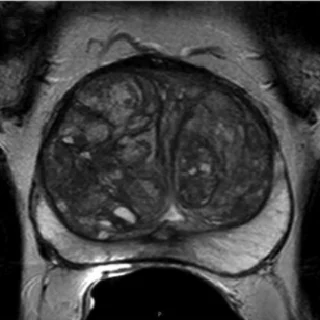

Transition Zone (TZ)

Нормальная ткань или круглый, полностью инкапсулированный узел (типичный узел)

Инкапсулированный узел или однородный ограниченный узел без капсулы («атипичный узел»), либо однородная гипоинтенсивная зона между узелками.

Неоднородная зона с нечеткими краями, все то, что не подходит в PIRADS 1-2 или 4-5

Вытянутой формы или не ограниченная гипоинтенсивная гомогенная зона, менее 1.5см

То же что и PIRADS 4, только размером более 1.5см или с распространением за пределы простаты